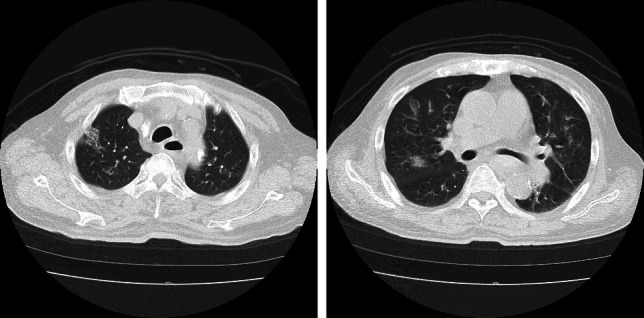

Seasonal influenza is prevalent globally, particularly during winter months. It is well documented that this disease causes severe, often fatal complications in hemodialysis patients. While numerous reports have focused on novel influenza viruses, there is a paucity of case reports detailing seasonal influenza viral infections in this patient population. This case presents a 71-year-old male undergoing hemodialysis who developed severe seasonal influenza A pneumonia despite receiving the influenza vaccine and early antiviral treatment. Initially presenting with fever, cough, and myalgia, the patient was diagnosed with influenza A virus infection and hospitalized due to heightened risk associated with dialysis and an elevated inflammatory response. Despite treatment with two different antiviral medications, his condition deteriorated, leading to ARDS (acute respiratory distress syndrome). The administration of steroid pulse therapy resulted in significant clinical improvement. This case underscores the severe nature of influenza virus-related illnesses in dialysis patients, even with vaccination and early antiviral intervention. It also suggests the potential benefit of early steroid pulse therapy in managing severe influenza pneumonia in high-risk individuals.